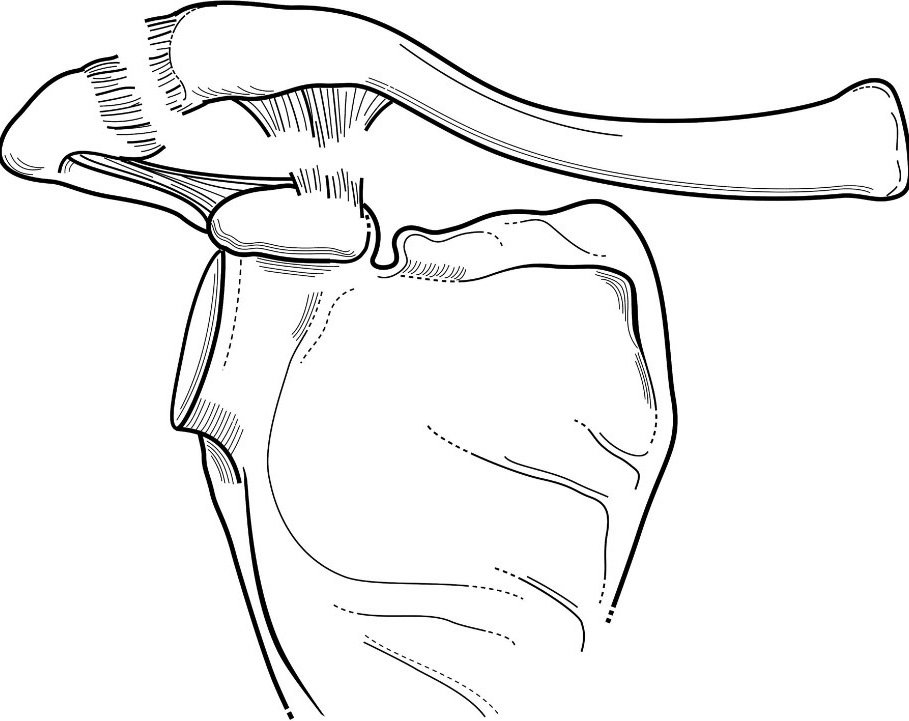

Figure 3 for case Grade 3 AC separation ( RID1895 )

Figure 3

Grade 3 AC separation ( RID1895 )